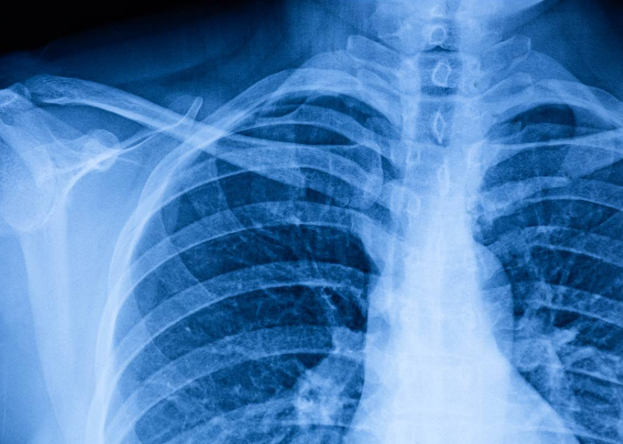

폐결절 CT 검사: 왜 반복해야 할까?

폐결절을 발견하고 나면 병원에서는 일정 주기의 폐결절 CT 추적검사를 권장합니다. 그 이유는 결절의 크기 변화, 모양의 변형, 새로운 결절의 발생 여부 등을 관찰하기 위함입니다.

CT 촬영 시 사용하는 방사선 양이 걱정될 수 있지만, 최근에는 저선량 CT가 활용되어 그 부담이 많이 줄어든 상태입니다. 방사선 노출보다 중요한 것은 결절의 진행 여부를 놓치지 않는 것이기에, 권고 일정에 맞춰 촬영을 진행하는 것이 좋습니다.

저는 6개월 간격으로 총 3회의 CT를 촬영했는데, 현재까지 결절의 크기나 모양에 변화가 없다는 소견을 받아 비교적 안정적으로 생활하고 있습니다.